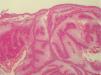

Pacientes 6 y 12La paciente 6 acudió a la consulta, en septiembre de 1998, por una pequeña pápula erosionada de color amarillento en la mejilla derecha, que fue diagnosticada clínicamente de carcinoma basocelular (fig. 1). En el análisis histopatológico de la lesión, se observó una neoplasia localizada en la dermis superficial, formada en su mayoría por sebocitos maduros que se agrupan de una forma desorganizada (fig. 2), que se diagnosticó de adenoma sebáceo. La historia familiar tenía varios casos de cáncer de colon y endometrio en familiares de primer y segundo grado (fig. 3) y cumplía los criterios de Amsterdam. La paciente se sometió a un programa de cribado para el cáncer de colon, con colonoscopias y exploraciones ginecológicas bianuales. Durante la realización de la primera exploración ginecológica, en enero de 1999, se detectó una neoplasia de endometrio que fue intervenida ese año mediante una histerectomía con doble anexectomía. Sus familiares de primer grado se sometieron también a un programa de cribado, aunque uno de sus hermanos lo rechazó. Durante el seguimiento de la familia, su hija (paciente 12; paciente III: 2) (fig. 3) presentó una lesión en la nariz clínicamente parecida a la de su madre, pero más pequeña, que fue extirpada en 2004 con 28 años de edad. La biopsia de la lesión mostró unos nódulos mal delimitados localizados en la dermis media, formados en su mayoría por sebocitos maduros y sin conexión con un infundíbulo en los cortes seriados (fig. 4), que también fueron diagnosticados como adenoma sebáceo. Ese año la familia fue remitida a un centro de referencia para realizar un estudio genético, detectándose una deleción en los exones 1 y 2 del gen MSH2 en la paciente 6 y en sus dos hijos, aunque uno de ellos no había presentado tumores en el momento de hacerse las pruebas (paciente III:1) (fig. 3). Dos de sus hermanos rechazaron hacerse las pruebas. No tenemos información sobre el resto de sus familiares, porque el seguimiento se realizaba en otros centros.